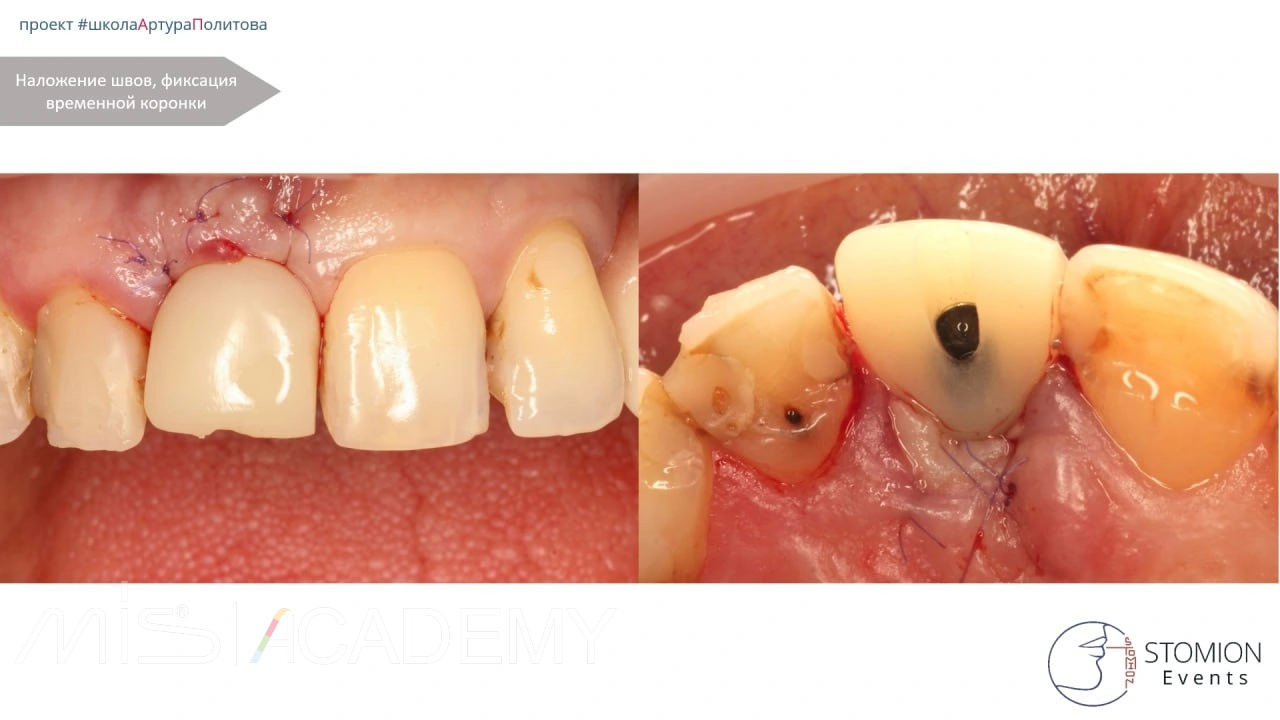

— Вестибулярно, в области свободного десневого края и сформированного кармана по типу «конверта», уложен деэпителизированный соединительнотканный трансплантат с целью профилактики коллапса мягких тканей.

— С нёбной стороны использован трансплантат с сохранённой эпителиальной полоской для компенсации дефицита мягких тканей.

— Выполнена немедленная нагрузка с использованием позиционера.

Снятие швов — через 9 суток.